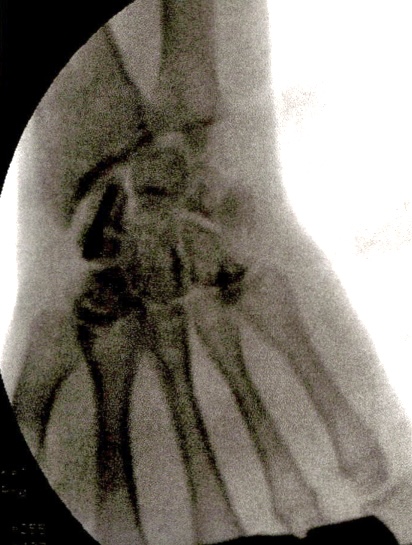

xx 男 36岁 腕舟骨骨折 掌侧切开复位内固定术 。

术前X片显示舟骨腰部骨折

术前X片显示舟骨腰部骨折,AO分型B2型。

掌侧入路

Herbert钉固定